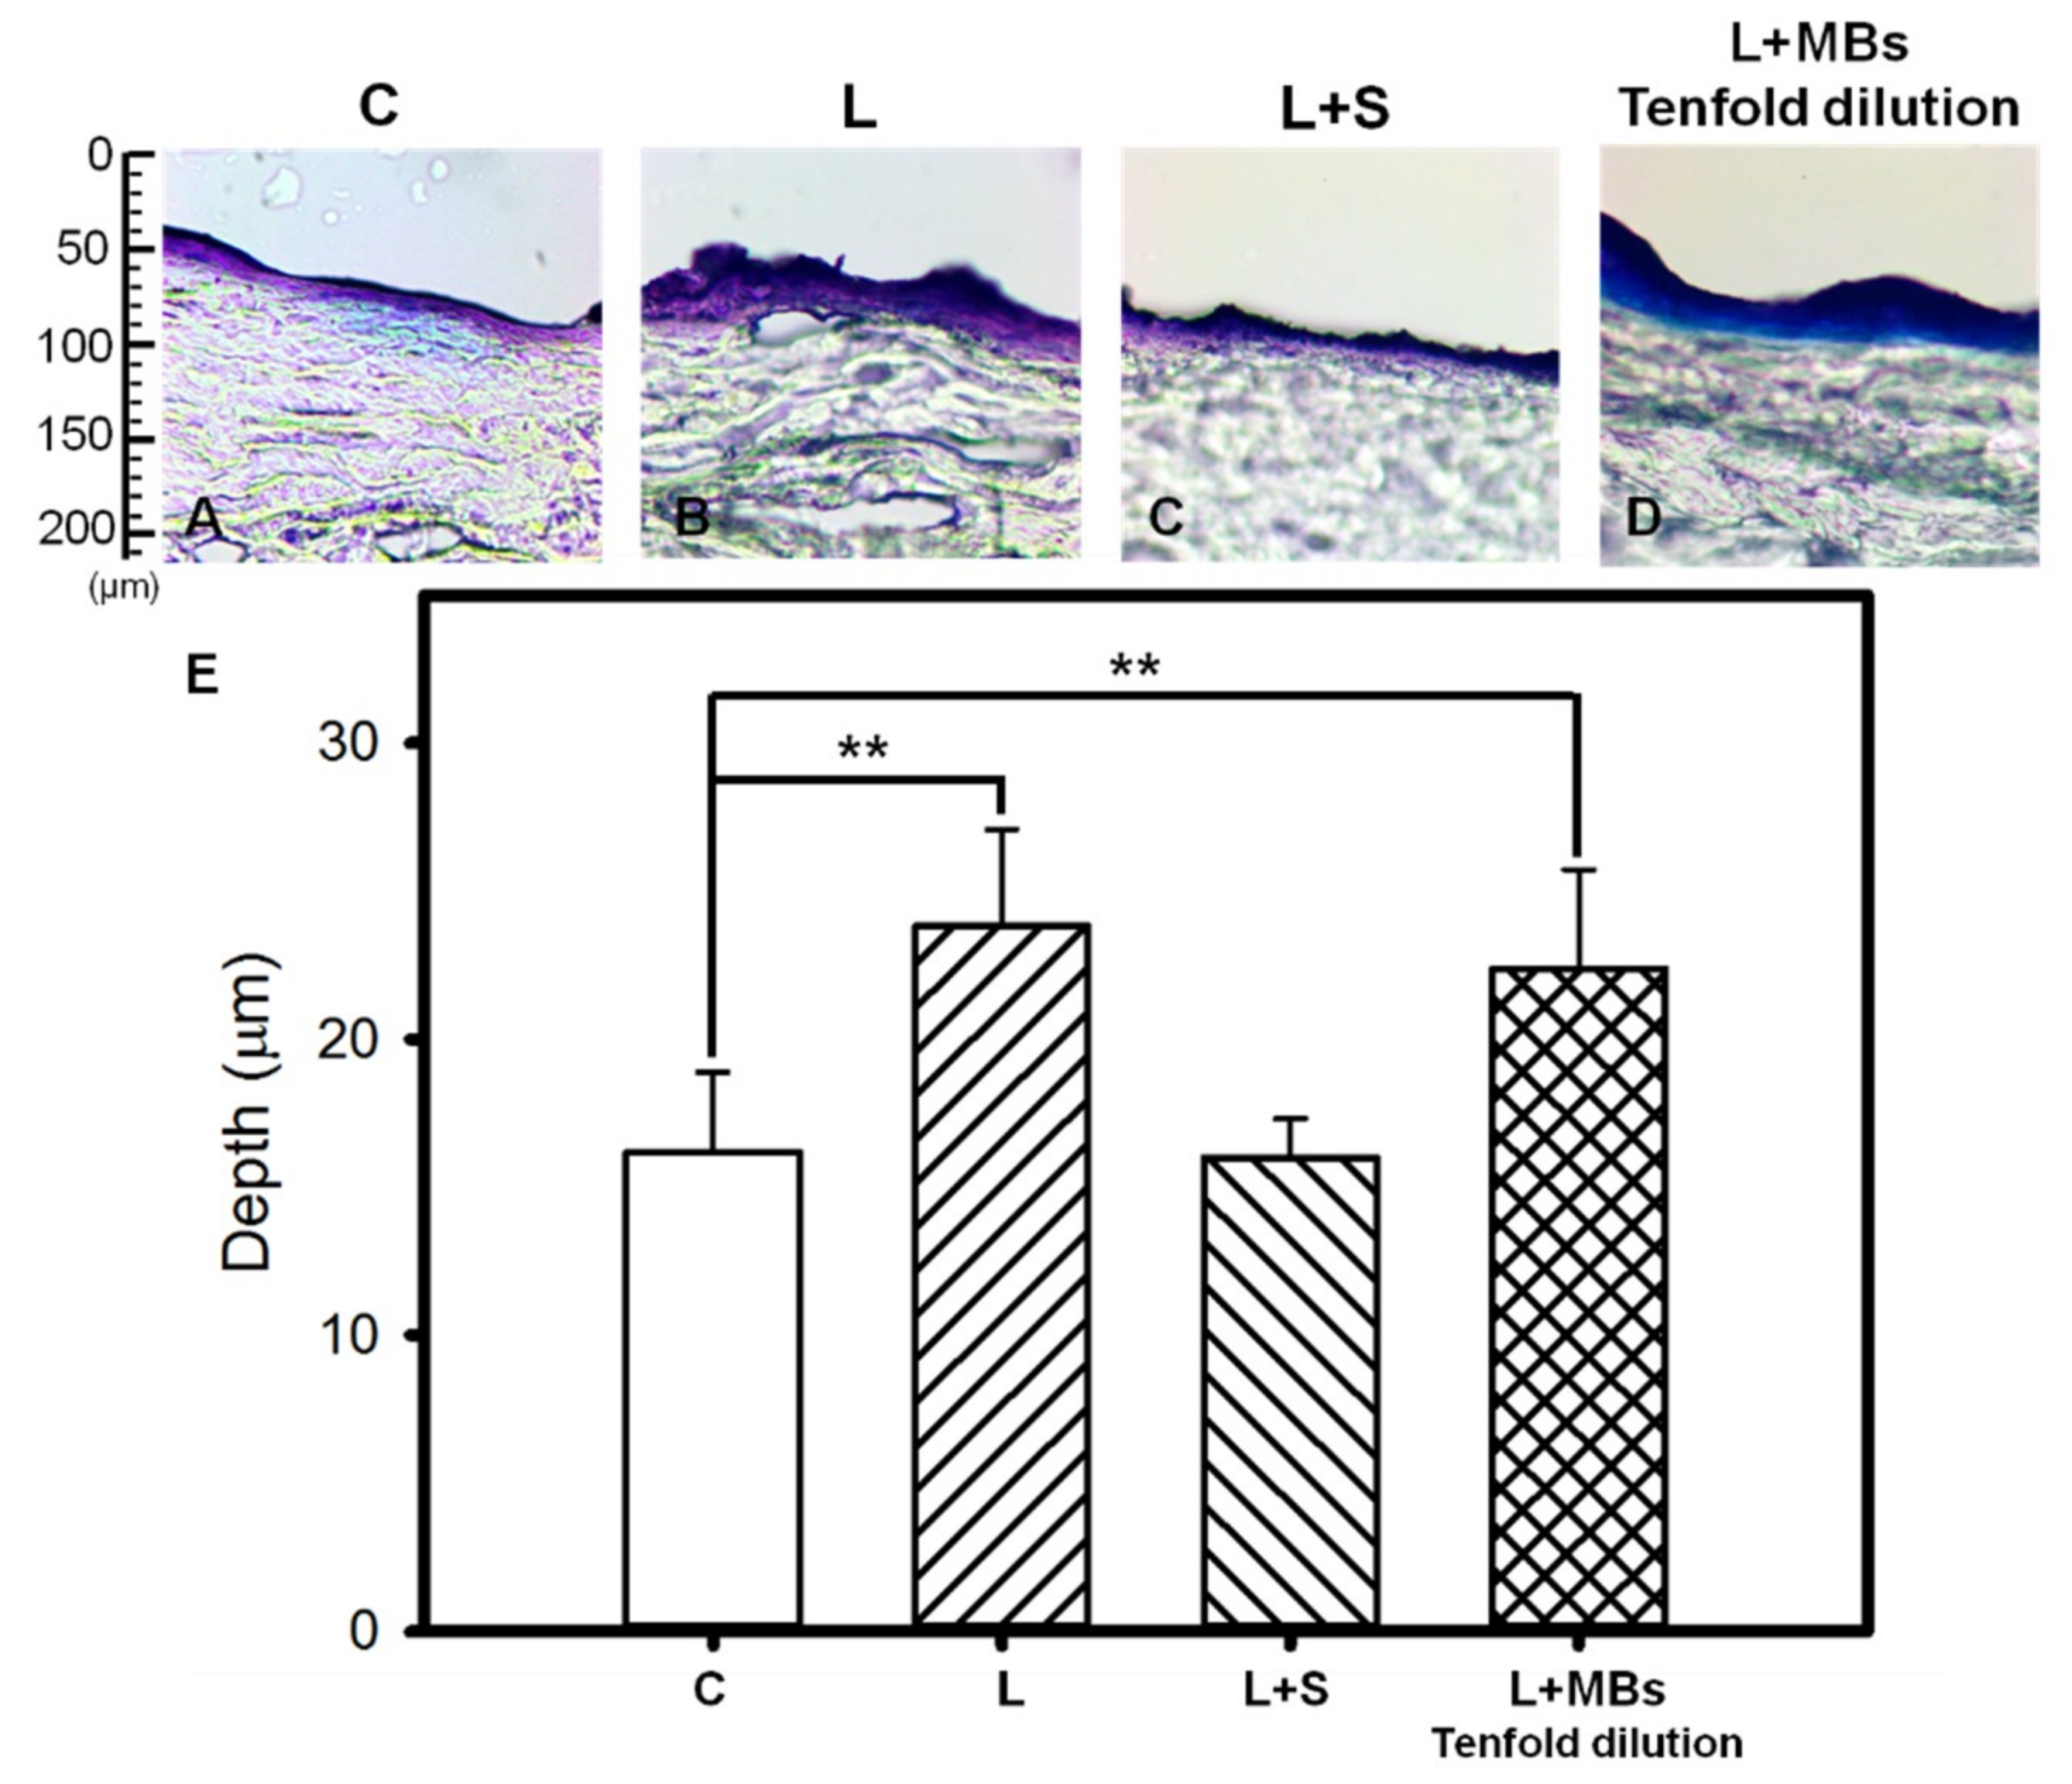

2.3. Penetration Depth in Pigskin

3.2. Penetration Depth in Pigskin

| Group | Skin Weight (mg) | Amount of β-arbutin Penetrated Across Skin (mg/mL) | Amount of β-arbutin Deposited on Skin (mg/mL) | Total Amount of β-arbutin Penetrated (mg/mL) |

|---|---|---|---|---|

| C | 18.88 ± 3.30 | 2.397 ± 0.07 | 2.291 ± 0.419 | 4.688 ± 0.491 |

| L | 23.43 ± 0.93 | 4.876 ± 0.017 | 2.559 ± 0.129 | 7.435 ± 0.146 |

| L + S | 18.75 ± 3.54 | 3.287 ± 0.01 | 3.355 ± 0.350 | 6.642 ± 0.451 |

| L + MBs | 22.47 ± 1.10 | 4.892 ± 1.14 | 3.292 ± 0.481 | 8.184 ± 1.628 |